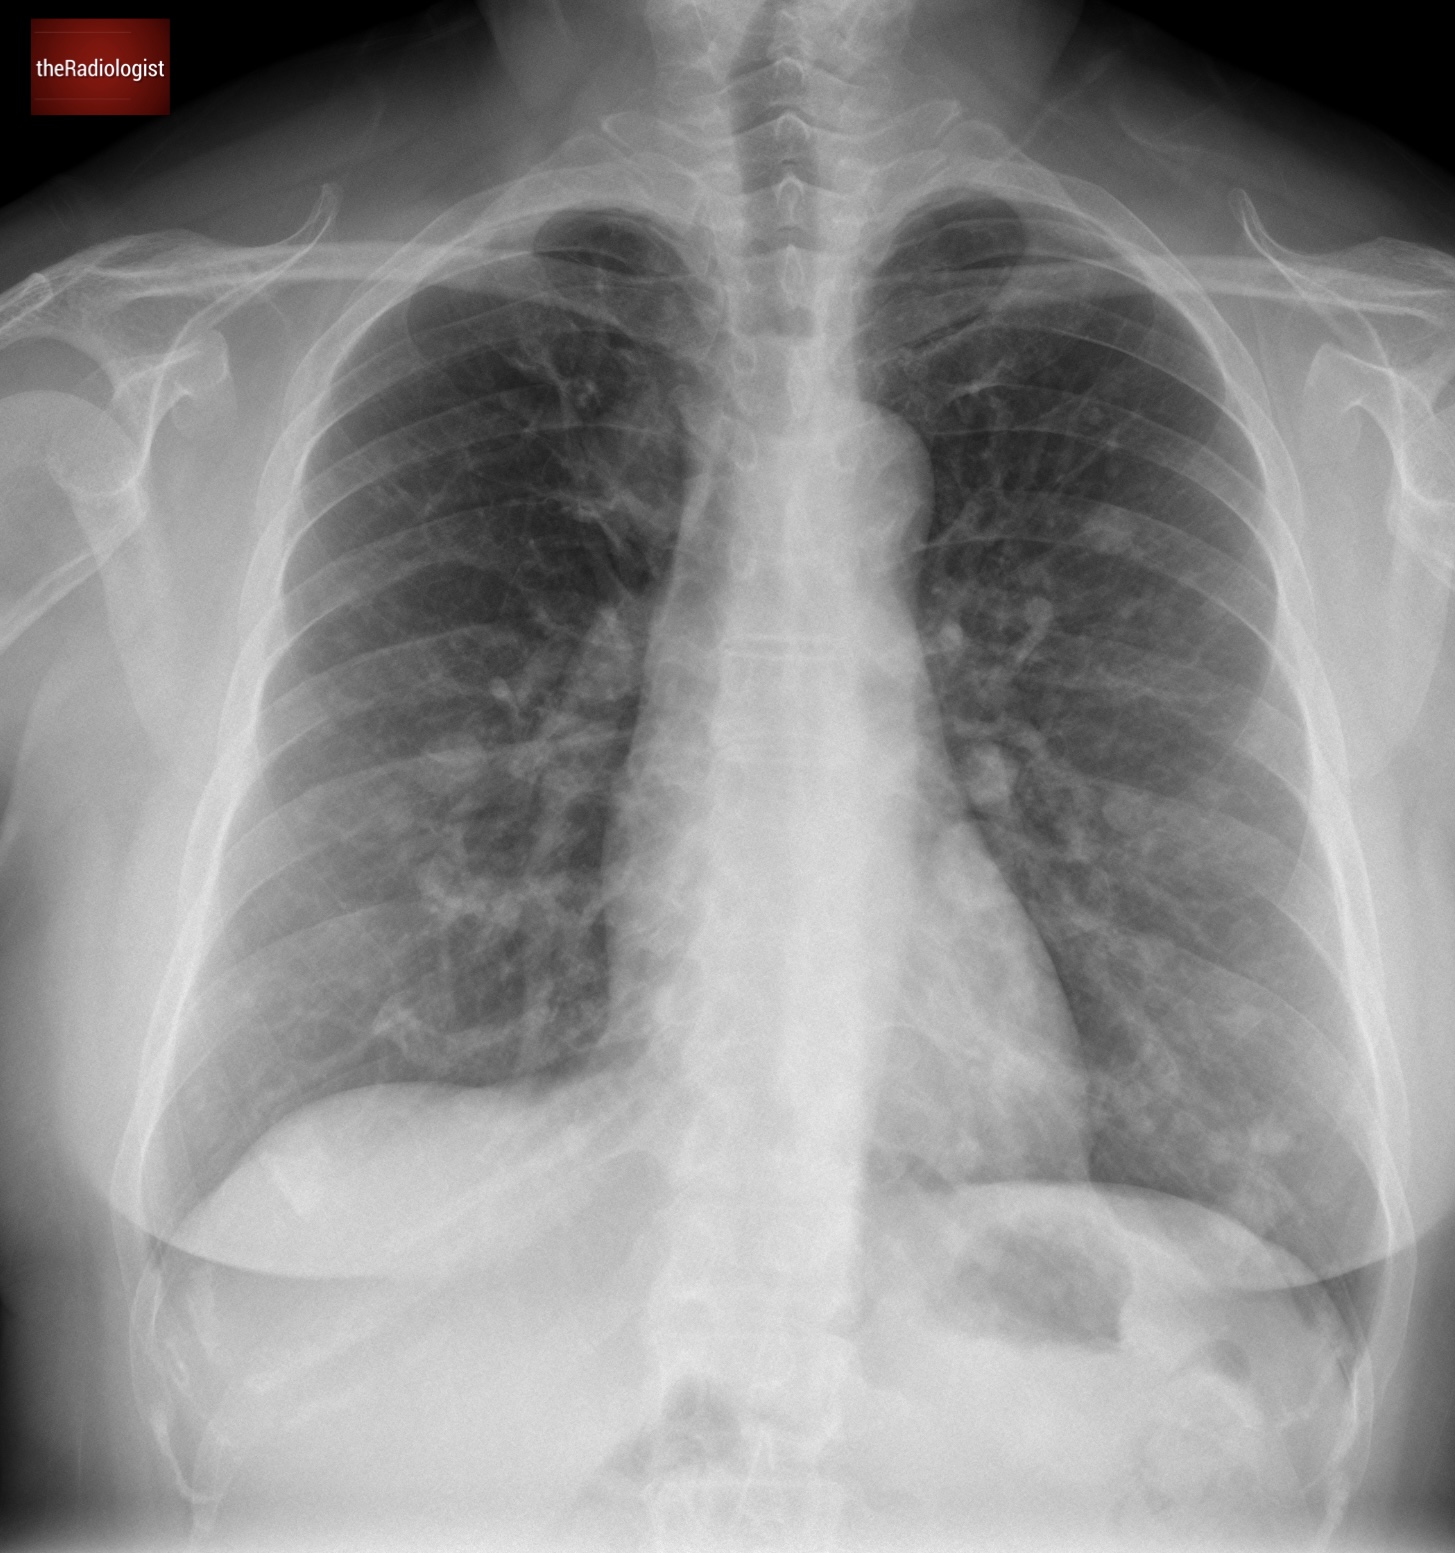

A 40 year old female presented to her local Emergency Department with chest pain and had a chest X-Ray. There was no significant known past medical history.

PA view of a chest X-Ray of a female in her 40s

The X-Ray shows multiple lung nodules. On the left, there’s a distinct nodule in the upper zone, and another larger one overlapping the heart border. Moving to the right side, we see a similar pattern, with multiple nodules scattered throughout.

We can see several well defined lung nodules within both lungs.